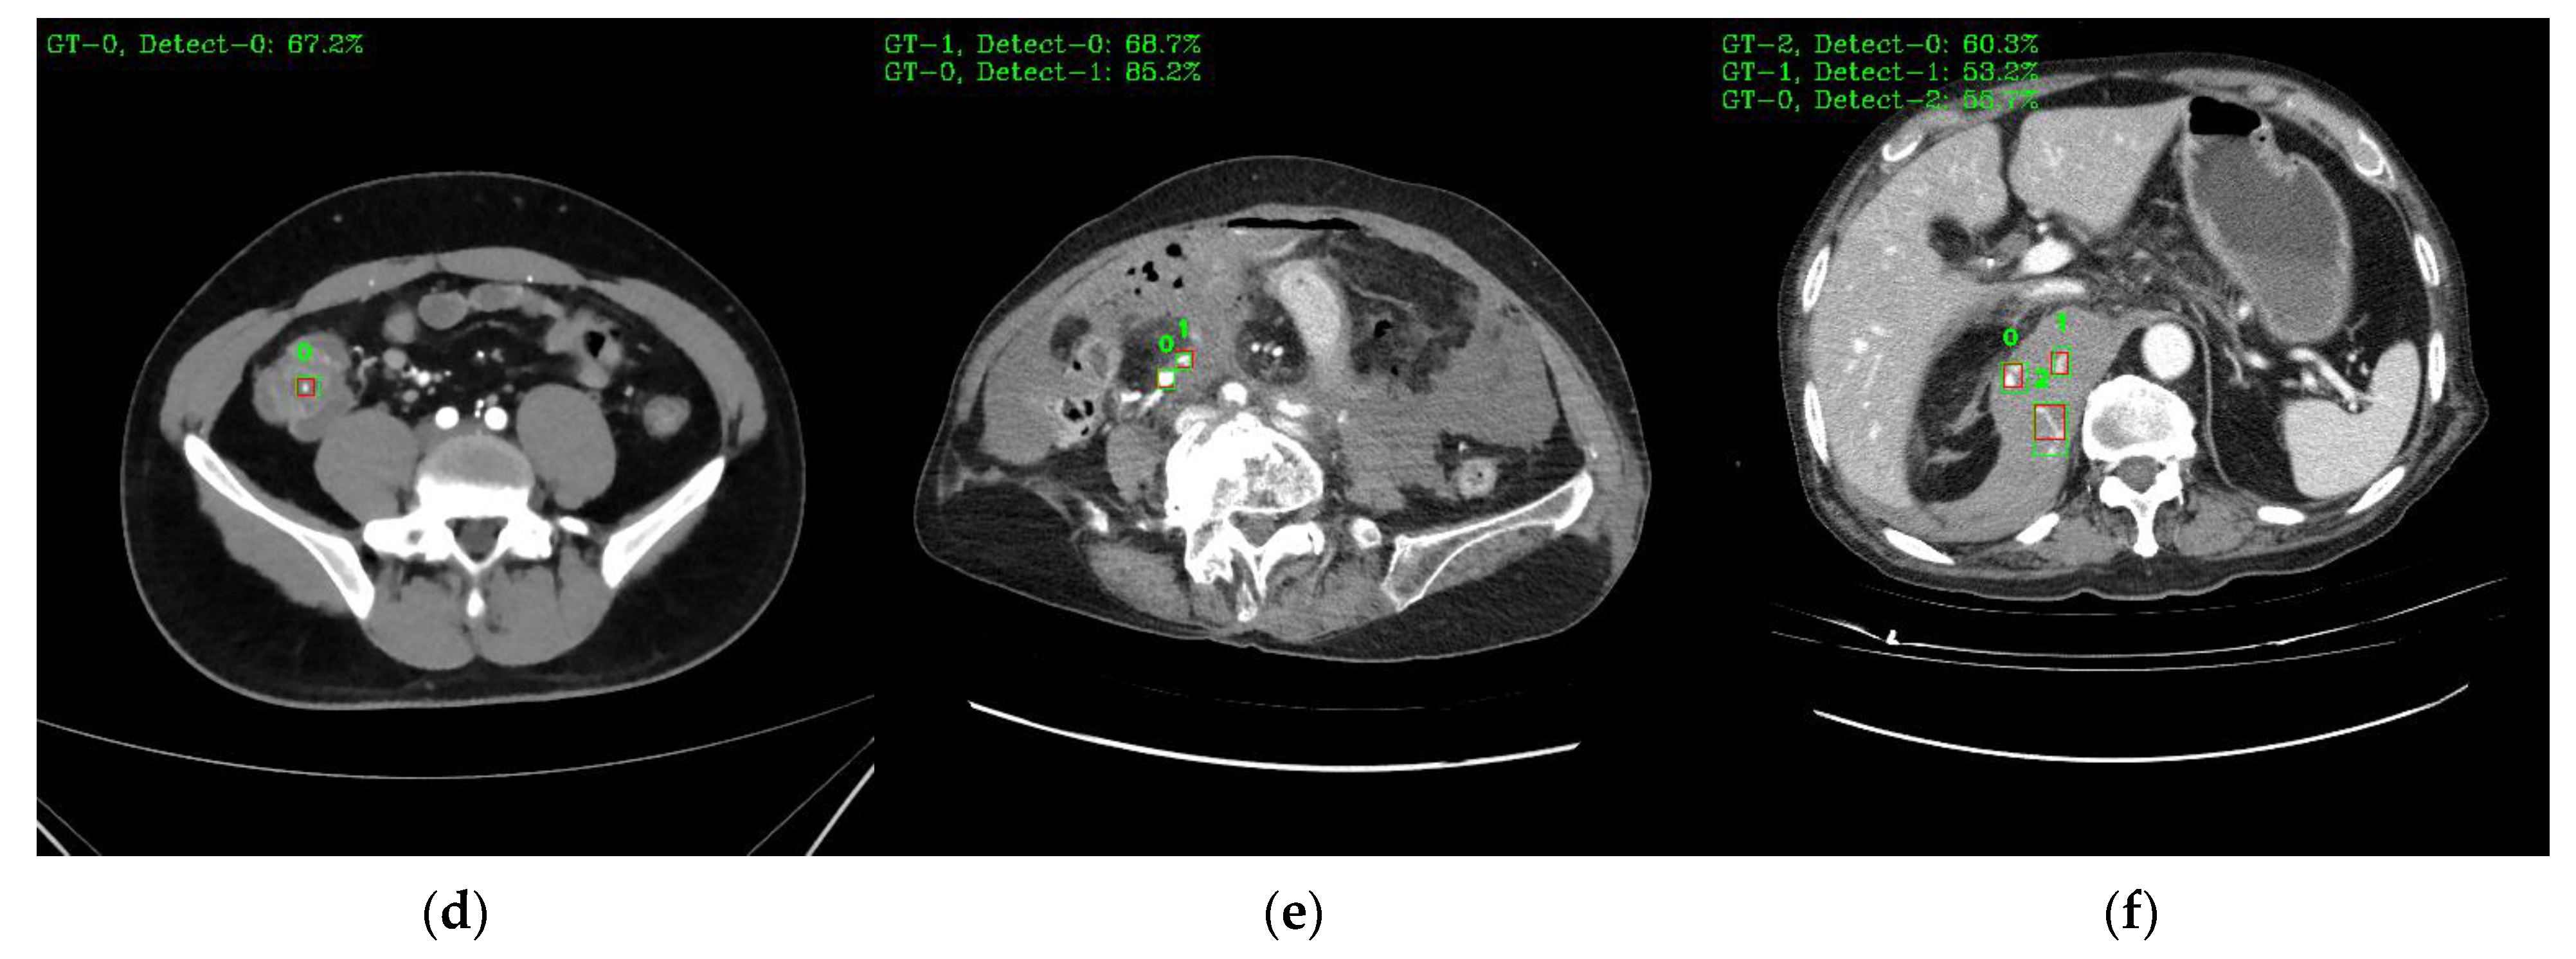

Figure 9 shows a visual representation of the results of lesion detection using the AH detector. Each image used for detection contains at least one GT-Box (green rectangle), which is the correct region. A P-Box (red rectangle), which is the detected region, is displayed according to the number of lesions detected and is not displayed when detection fails. The green text in the upper left corner of each image shows the index number of the GT-Box, index number of the detected P-box, and information about the IoU score. For example, Figure 9a shows that, for one GT-Box with a GT-Box index number of 0 (GT-0), two P-Box index numbers (Detect–{0, 1}) were generated with IoU scores of 76.8% and 42.8%. In addition, as shown in Figure 9c, out of the four GT-boxes with GT box index numbers GT–{0, 1, 2, 3}, only GT–{1, 3} was successfully detected, resulting in P-boxes with IoU scores of 69.8% and 79.6%, respectively.

Figure 9.

Example images of the AH-lesion detected using the AH detector. Green boxes indicate GT-Box, and red boxes indicate P-Box. Green text is GT-Box index, P-Box index, and IoU score: (a) single GT-Box and detected two P-Box; (b) two GT-Box and detected each single and two P-Box; (c) four GT-Box: detected two P-Box and missed two P-Box; (d) single GT-Box: detected single P-Box; (e) two GT-Box: detected two P-Box; (f) three GT-Box: detected three P-Box.